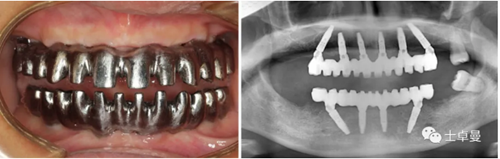

鈦支架口內(nèi)試戴及X線檢查;

【病例分享】應用全程數(shù)字化對牙周炎患者實現(xiàn)全口即刻種植即刻修復

永久修復體戴入后的口內(nèi)相及唇齒關系;